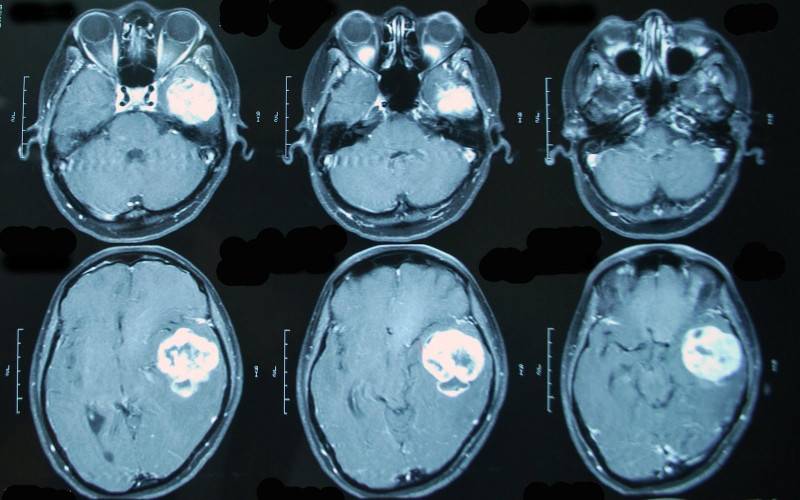

МРТ головного мозга с контрастом обязательно при диагностике онкологических процессов.

Их вводят пациенту внутривенно прямо во время исследования. Они быстро разносятся кровью по организму, накапливаясь в опухолях, потому что к ним приток крови, как правило, сильнее. Применение контраста позволяет значительно лучше визуализировать сосуды и капилляры. Особенно актуально это при исследовании сосудов, головного или спинного мозга, органов малого таза.

На основании этих проекций формируется представление о реальных физических размерах, взаимном месторасположении, структуре и состоянии любого внутреннего органа. По МРТ-снимку можно локализировать опухоль с диаметром от 1 миллиметра, найти внутреннее кровотечение, травматическое изменение в тканях или патологию их развития, очаг воспаления и зону инфекционного поражения. Если во время сканирования в кровь пациента ввести контрастное вещество, проекция виртуального среза станет более отчетливой — диагност наведет «резкость» на снимке, повышая точность прогнозов.

Процесс проведения МРТ с контрастом

Пигментное вещество, вводимое в кровь пациента, заставляет ткани новообразований изменить цвет на мониторе томографа, проявляя себя даже при незначительном размере опухоли. Контраст подсвечивает метастазы, вскрывает проблемы послеоперационного периода, фиксирует кровотечения и аномальные скопления жидкости в тканях, окружающих внутренний орган.